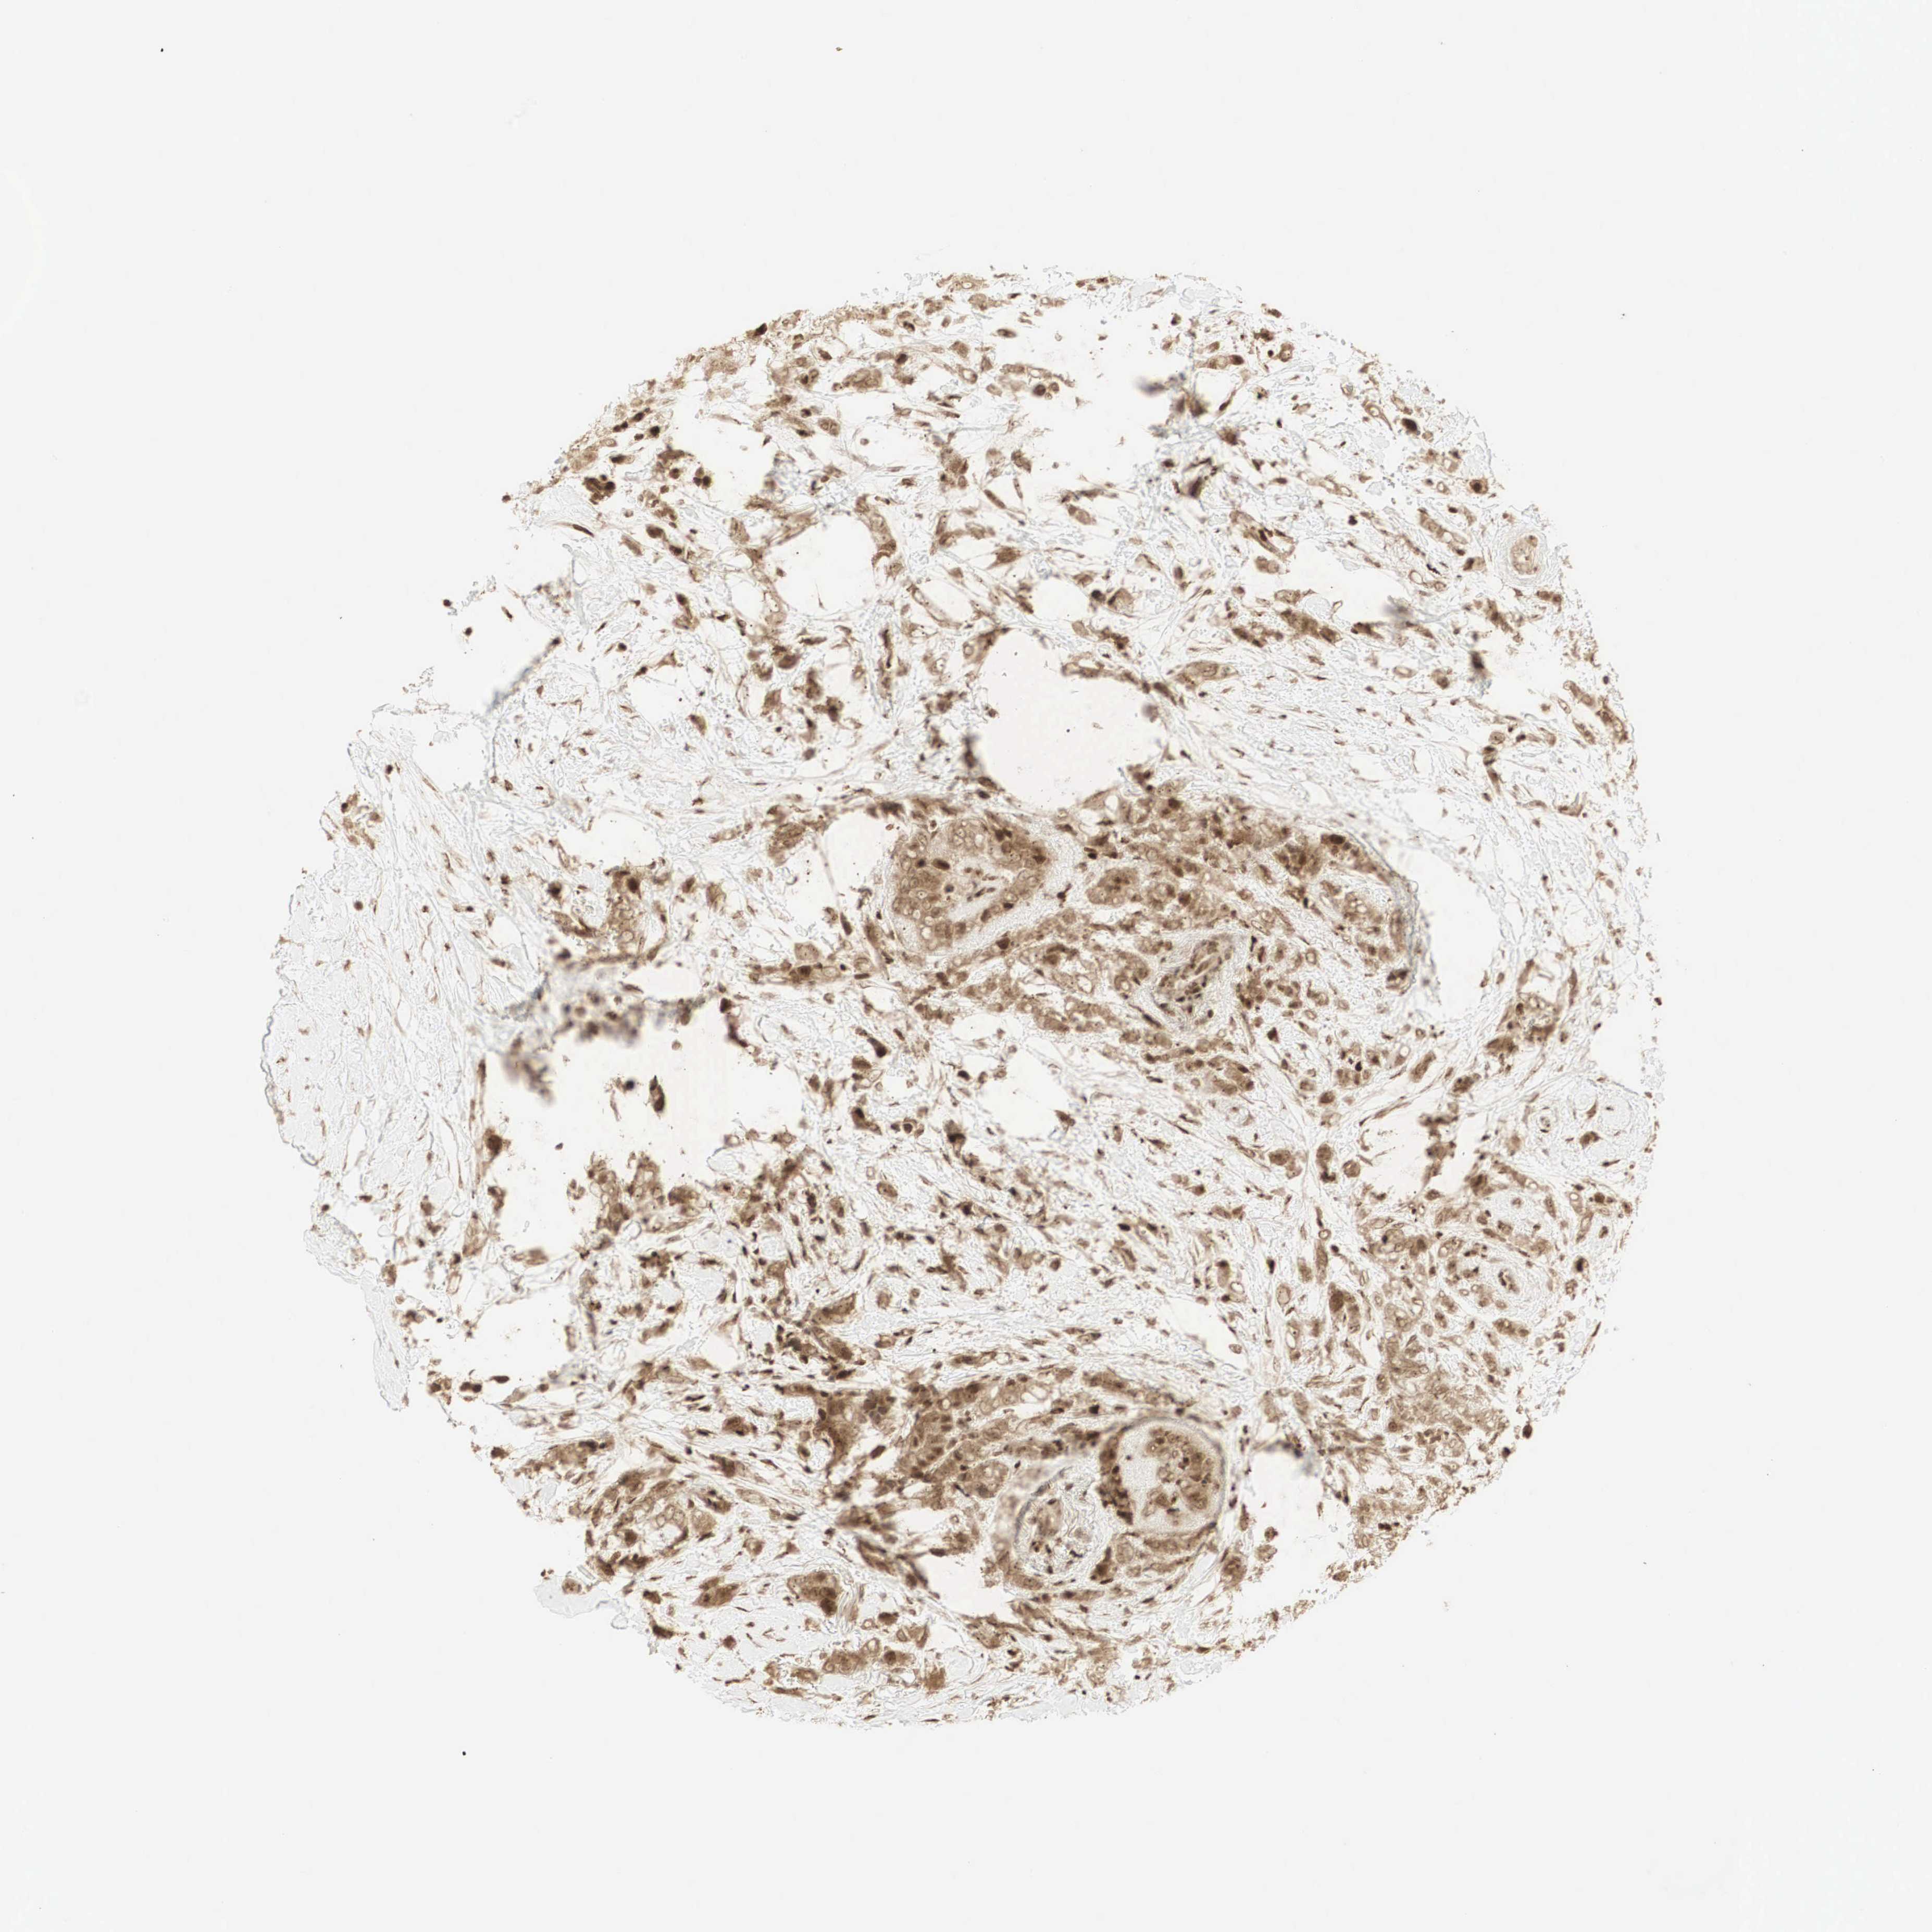

CANCER BREAST CANCER Show tissue menu

BRCA TCGA BRCA VALIDATION PROTEIN EXPRESSION